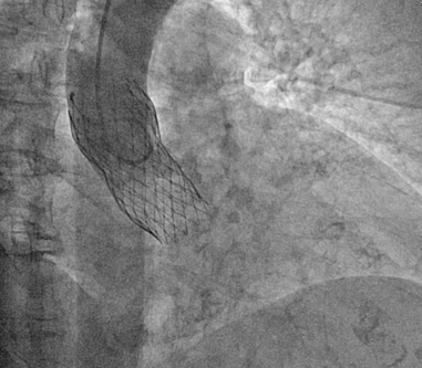

- Specific analysis services: Angiography (coronary and peripheral),Intravascular imaging (OCT- IVUS), QFR, iFR, MRI, Echocardiography (TTE, TEE), CT-scan (aortic & mitral valves, peripheric), Cardiac MRI, ECG and, aortography.

- Quantitative and qualitative assessments (Angiography, QCA, IVUS, OCT, QFR, ECHO, CT scan, MRI, ECG)

Aortography